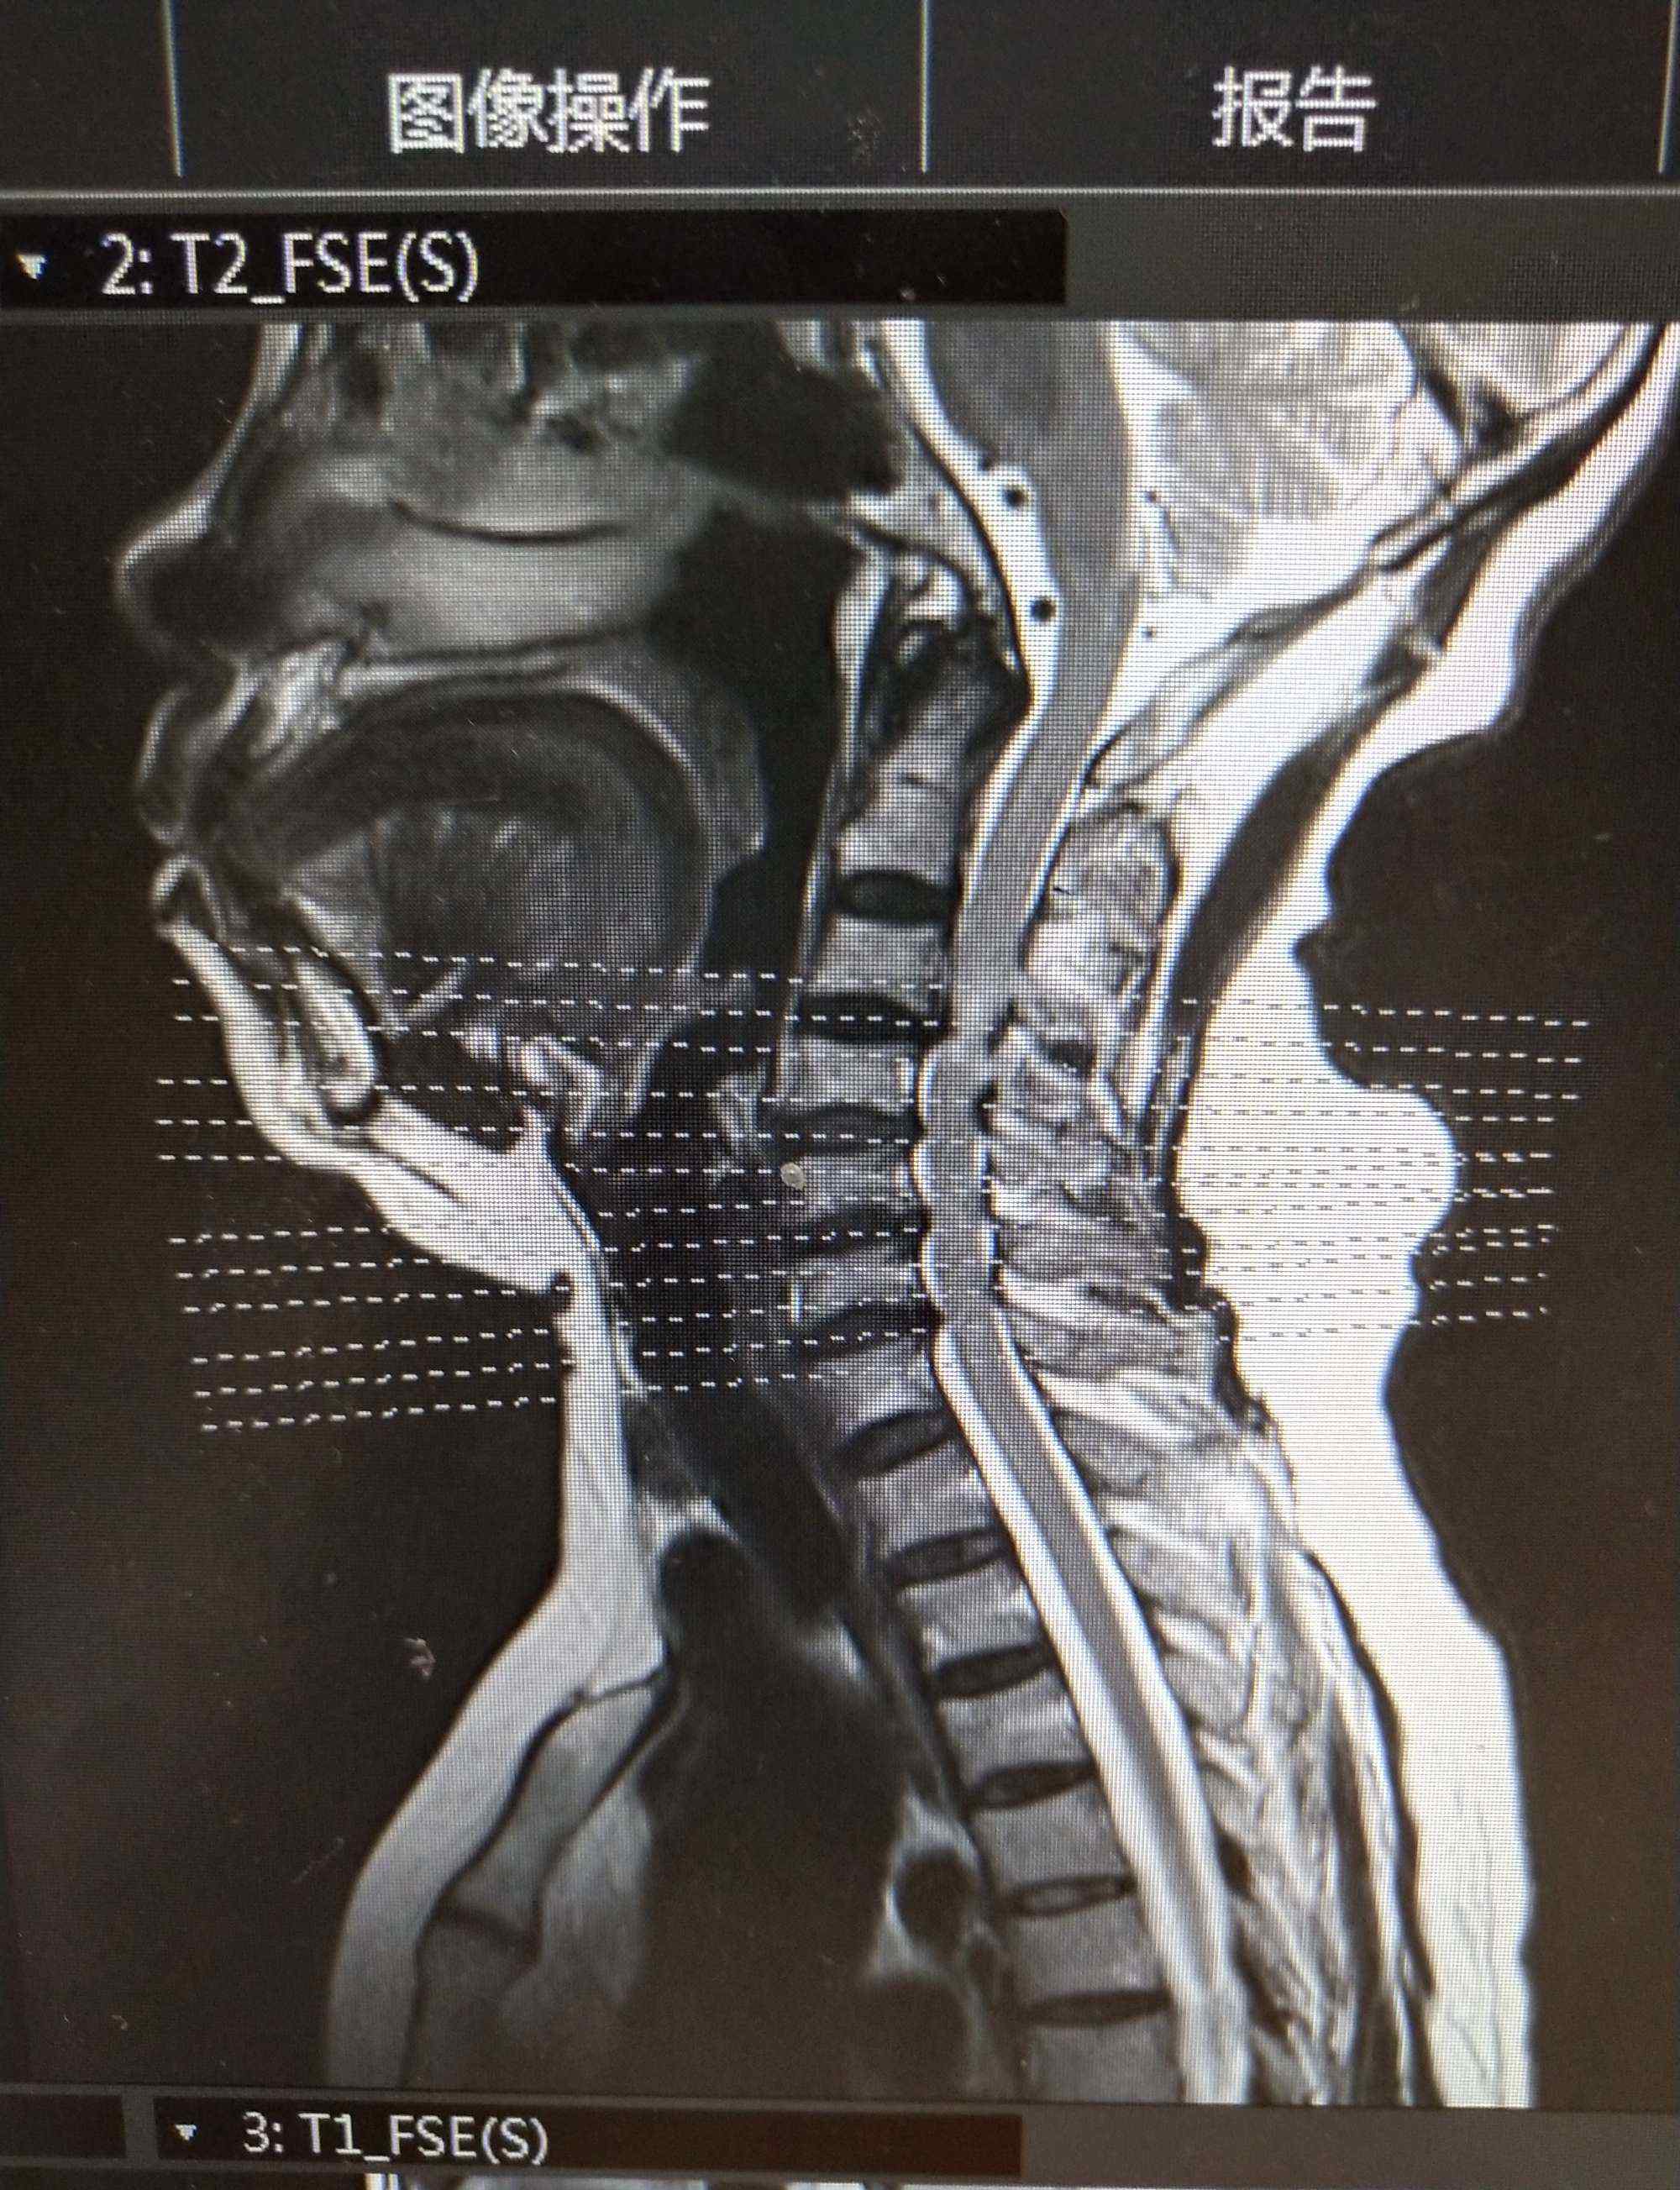

MRI